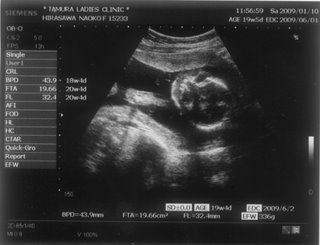

お腹の赤ちゃんは、今日で24週と4日。あっという間に7ヶ月突入です

![]() お腹もドンドン、食欲もドンドン出ていてあしたの4回目の検診コワーイ ![]() 妊娠発覚から三ヶ月半、なのにもう妊娠7ヶ月!頭がついていきません ![]() でも、毎日激しくなる胎動に感激している日々です ![]() 一回目の検診から4週後、2度目の検診に行ってきました。 2008年12月13日 赤ちゃんは15週と5日 ![]() 順調でした ![]() 左側から頭、胴体、足が写っていまーす ![]() 今回は4Dの機械も入り毎回撮影してくれるそうでーす ![]() 赤ちゃんは、ゴツゴツした背中だけを 見せ、顔はみせてくれませんでした~ ![]() それから4週後、3回目の検診。 2009年1月10日 赤ちゃんは19週と5日 ![]() 336gくらいになったようです ![]() 4D ようやく顔をみせてくれました ![]() かなりエイリアン ですが、フニュフニュ可愛かったです![]() 性別が わかりそうだったんですが、ソラ同様肝心なトコロをみせてくれませんでした ![]() もちろんどっちでもいいんですが、しりたーい ![]() 明日わかるかな ![]() ソラも赤ちゃんがテレビに映ったり、雑誌に載っていたり、 出かけ先で見かけたりすると、「ベイビー ![]() 」と大きな声で、何度も何度も興奮気味に言います ![]() 自分もまだまだ赤ちゃんなのに、「ベイビー」は自分より 小さくて可愛いものだと感じ始めているようです ![]() わたしは、一週間に1度だけ1歳になったばかりの 女の子を預かっています。 ソラは、その子が自分のオモチャを使うことに対して 少しイヤな気がしているようです ![]() 少し前までは「ドーゾー」と相手に有無を言わせず 何でも渡していたけど、どんどん自我が出てきているみたいですね~ そんな感じでオモチャを取り合いしながら、シェアすることも学んでいます。 でも女の子が寝ると、さすがに可愛いと思ったらしく、 頭をナデナデ、チュしていました ![]() 妊娠検査薬で妊娠反応がプラス |